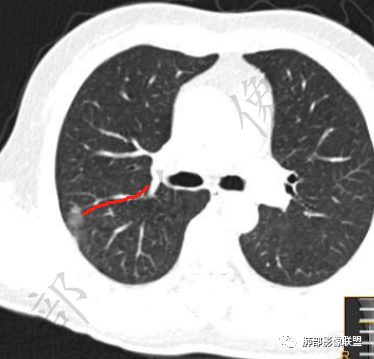

2、影像所见:右肺上叶后段混合密度磨玻璃影mGGN,整体膨隆为主,局部收缩,局部边缘可疑月牙铲。周围磨玻璃影边界清楚,边缘分叶,细细观察这种清楚的弧形边界,与小叶间隔是否高度契合?!

结节内血管影增粗。病灶附近血管纠集,临近胸膜轻度增厚,叶间胸膜轻度牵拉移位。综合考虑恶性,腺癌可能。(局部胸膜增厚,考虑为肿块局部牵拉为主造成的)。

3、鉴别诊断:本例最需要鉴别的就是隐球菌感染,支持点有病灶位于胸膜下,长轴似乎平行于胸膜,周围有磨玻璃样晕征。不支持点是周围磨玻璃影边界清楚,这一点更支持腺癌。